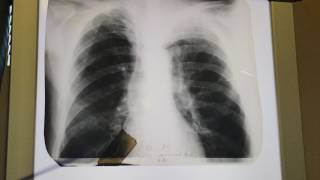

Рак прямой кишки Т2NхM0. Хирургическое лечение